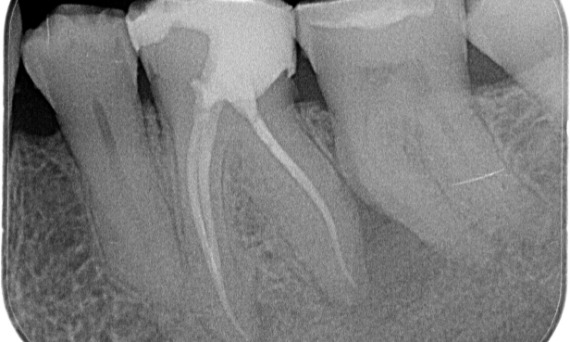

Przed: Przejaśnienie okołowierzchołkowe związane głównie z korzeniem dystalnym i utrata blaszki zewnętrznej zbitej na korzeniu mezjalnym.

Po: W tym przypadku wybrano TruNatomy, aby umożliwić podejście oparte na wykorzystaniu ubytków próchnicowych i skupienie się na zachowaniu zębiny okołoszyjkowej, szczególnie w części mezjalnej, gdzie ząb miał bardziej minimalną odbudowę.